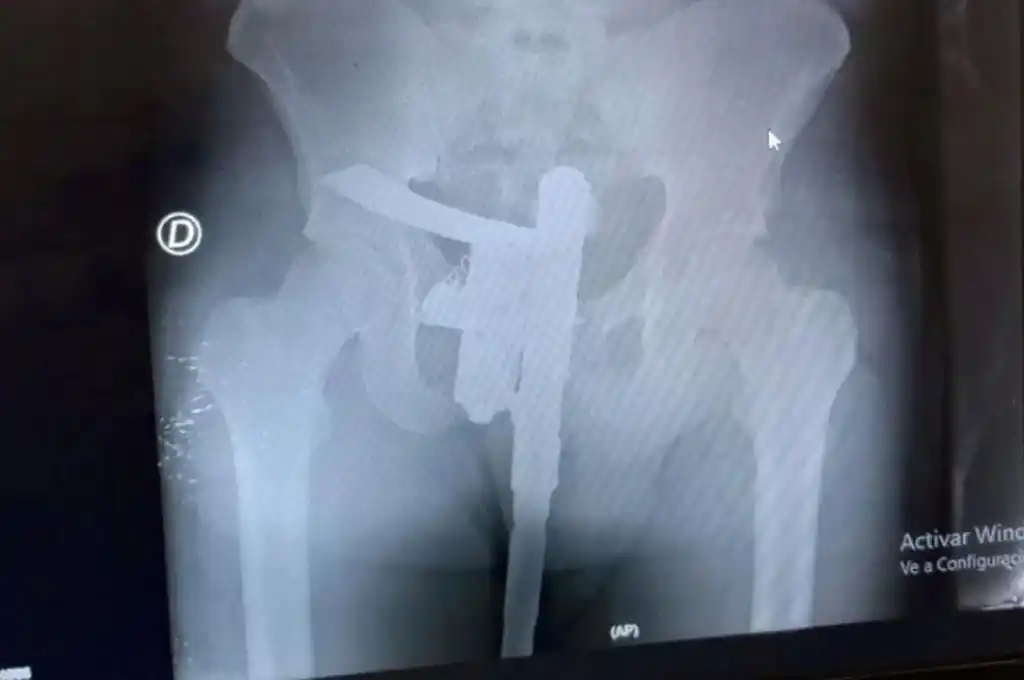

El estudio se concretó de manera normal, aunque minutos después el revelado permitió descubrir una “sorpresa”. En la placa se observó que el paciente tenía un arma de fuego oculta entre sus genitales.

Como es de rutina un médico hizo una primera evaluación y, como el paciente manifestaba dolor en la zona de la cadera, se ordenó realizar una placa radiográfica.